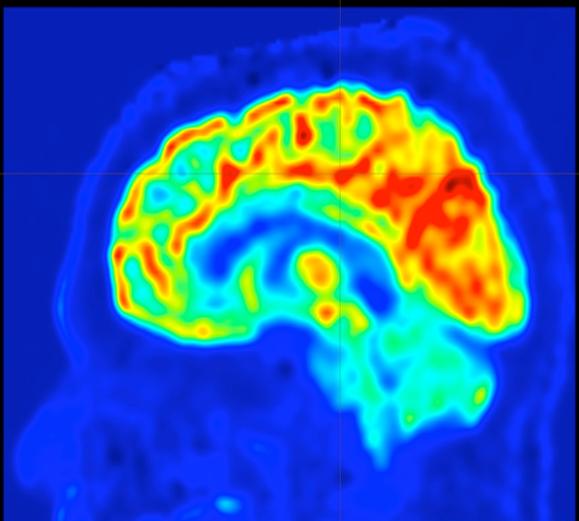

A brain map, created by a new approach developed at UVA, to guide surgery to prevent epilepsy seizures.

UVA’s new approach uses an enhanced form of positron-emission tomography (PET) to measure glucose use in the brain. This allows doctors to pinpoint the trouble spot in the brain that is triggering seizures. Once that spot is identified, it can be removed surgically, stopping the seizures.

PET scans have been used in the past to identify epilepsy trouble spots, but such scans have limited accuracy and often fail to identify an appropriate target. So a team of UVA researchers, backed by the UVA Brain Institute, developed the new approach, called “parametric dynamic FDG-PET imaging” (p-dFDG-PET).